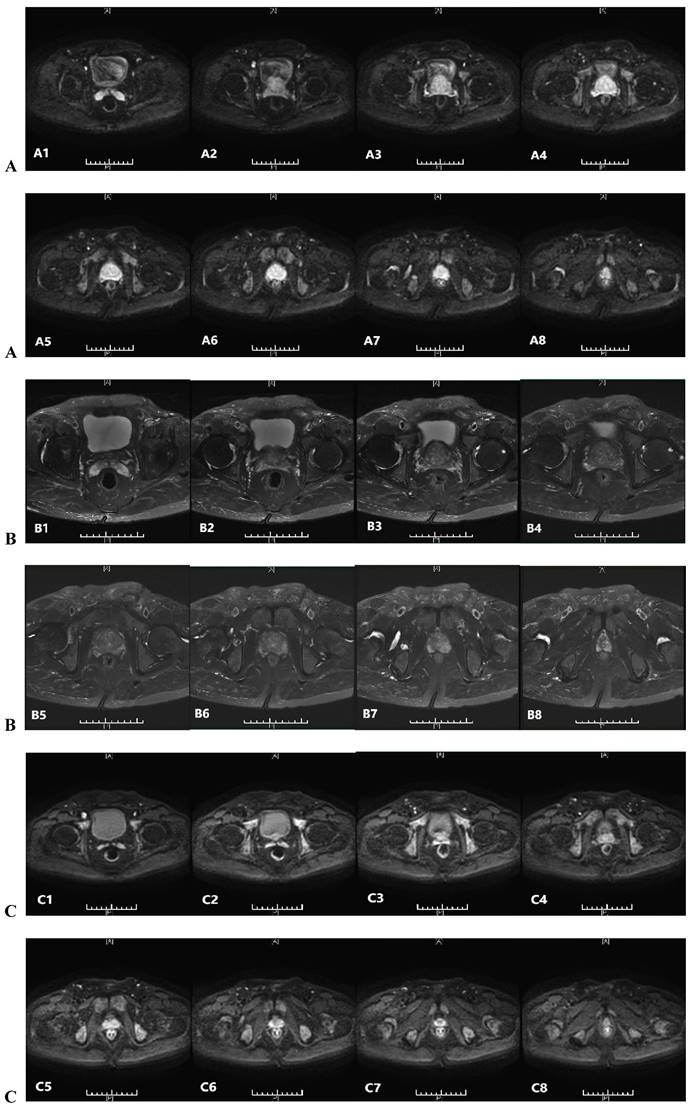

The histopathological study of prostate adenocarcinoma in Group A after pTURP were shown in Figure 1. The comparison of erythrocyte and leukocyte counts at the 3rd, 6th, 9th, and 12th weeks after pTURP in group A patients were shown in Figure 2. Postoperative MRI examination showed that the morphology of the prostate was significantly smaller than that before surgery, as shown in Figure 3. The five-year cumulative survival rate was 100% (15/15), as shown in Figure 4. Nine cases achieved tumor free survival. Their post-operative serum TPSA were lower than 4ng/ml continuously. Their MRI and CT results showed no local recurrence and metastasis. Five cases still followed up for more than 8 years. The oldest of whom is 91 years old now. They didn't use ADT anymore. Five-year PSA progression-free survival was 93.33% (14/15), as shown in Figure 5. The serum TPSA of this PSA progression case was greater than 10ng/ml in the fourth year after surgery. MRI showed that there was a single pelvic metastasis, but there was no fracture. Another case had a little urinary incontinence during daytime activities, but no urinary incontinence at night. One pad/day was needed for him. No complaints of frequent urination and difficulty urinating. According to the re-examination of urodynamics, the patient had detrusor instability and normal bladder capacity. The incidence of urinary incontinence and other complications in all cases receiving pTURP was low and the satisfaction was high. The average intermittent ADT was 23.93 months (95%CI 11.15∼36.72).

Figure 3

Prostatic MRI of a patient of group A: A(A1-A8) pre-treatment DWI indicate high signal nodule in the prostate. B(B1-B8) pre-treatment T2WI indicate low signal nodule in the prostate. C(C1-C8) post-treatment 5 years DWI indicate no high signal nodule in the prostate. D(D1-D8) post-treatment 5 years T2WI indicate no low signal nodule in the prostate.